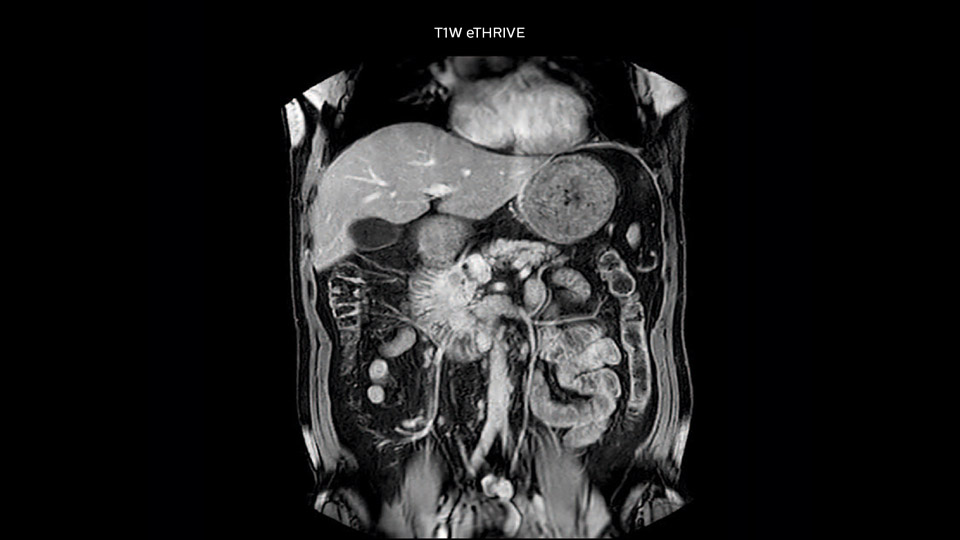

In this example the image quality of the MultiVane XD images is evidently better than in the images without MultiVane XD. Ingenia 1.5T with dS Torso coil solution.

“Our liver exams are quite fast,” says Dr. Baumann. “If the patient tolerates it, we use an arms-up position to reduce the FOV and speed up the exam with dS SENSE.” “We acquire one transversal high resolution T2-weighted sequence with 3 mm slice thickness, for example for pancreas or liver lesions. Then we also add a T2 fat suppressed MultiVane XD SPIR sequence. We perform these two routinely in our liver imaging. We use high dS SENSE factors to significantly shorten scan times to 2-4 minutes, which can improve our protocol; it’s a very robust scan.” “We include mDIXON for the dynamic sequences because of the robust and homogeneous fat suppression we get with that. We had been using eTHRIVE, but we are now quite happy with mDIXON. Sometimes we use a medication to calm the bowels, to further improve the image quality.”